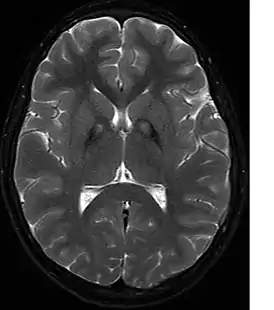

![]() На МРТ изображены отложения железа в базальных ганглиях. | |

Необходимо биохимическое исключение болезни Вильсона-Коновалова, факультативно — исключение нейроакантоцитоза, прежде всего с помощью МРТ. В МРТ в Т2- взвешенных изображениях являются типичными — обусловленные отложением железа — гипоинтенсивные очаги в бледном шаре, с центральным очагом гиперинтенсивности — так называемые «глаза тигра». Этот симптом обнаруживается у всех больных с PANK2-мутациями. В генетическом обследовании могут обнаруживаться мутации в PANK2-гене. Тем не менее, уверенно можно говорить о диагнозе только после патологоанатомического исследования.